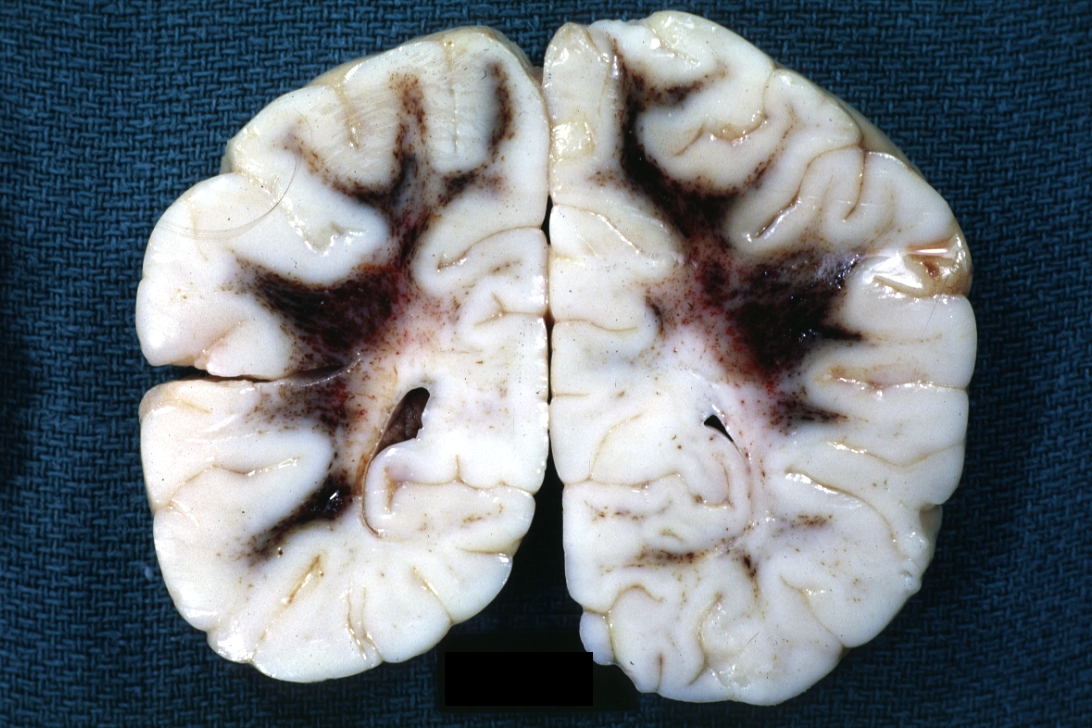

GROSS: NERVOUS: Brain: Bilateral Centrum Semiovale Hemorrhages: Gross fixed brain infant